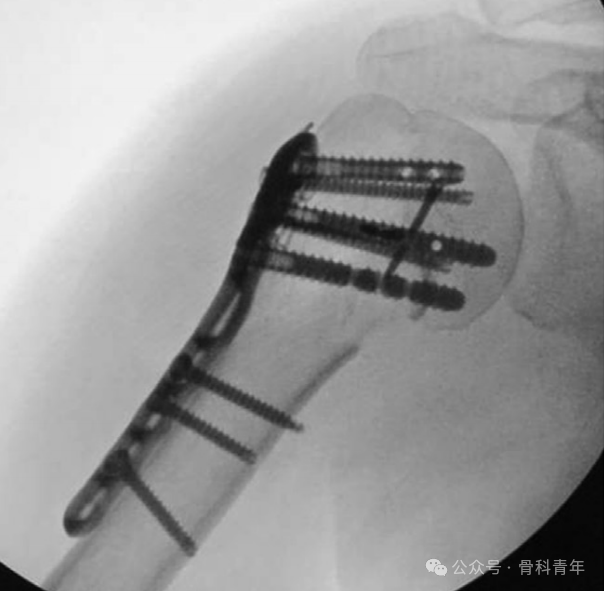

该手术的特点在于此特殊的低切迹钢板:钢板厚2.8mm,长73-220mm,3.5mm皮钉长10-45mm,5.28mm全螺纹钉长30-50mm,1.5mm交叉螺钉长20-35mm。钢板侧方具有便于缝合肩袖的侧夹,小螺钉可穿入近端5.28mm粗螺钉中。

常规三角肌胸大肌入路,复位骨折并临时固定后,将钢板放置于肱骨结节间沟后方,距离大结节顶点1-2cm,常规固定远近端螺钉。后通过外界导向架,经近端螺钉内置孔,置入1.5mm交叉螺钉(钉中钉)。